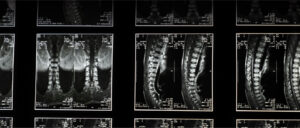

Coluna Vertebral

Indivíduos que sofrem com dores crônicas, hérnias de disco, ciatalgia, fraturas ou tumores na coluna, e que necessitam de diagnóstico e tratamento para alívio da dor e melhora da mobilidade.

Dr. Everson Akio Sakô

A coluna vertebral é a estrutura central do esqueleto humano, responsável por sustentar o corpo, permitir movimentos e proteger a medula espinhal. Composta por 33